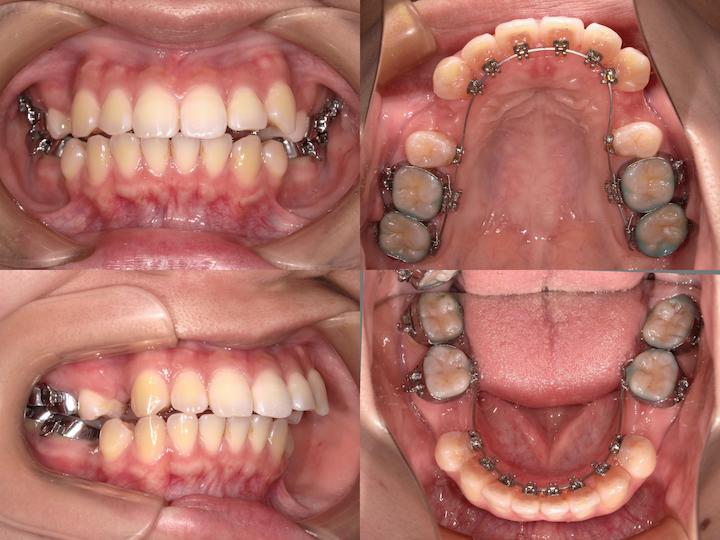

上下顎ともに舌側矯正装置(リンガルブラケット)を使用し、審美性に配慮した治療を実施いたしました。アンカレッジコントロール

上顎においては、犬歯の後方牽引時における大臼歯の不要な近心移動を防止するため、正中口蓋縫合部にPLAS(パラタルレバーアームシステム)を植立し、マキシマムアンカレッジ(最大固定)を確立しました。これにより、上顎大臼歯を確実に固定し、治療後の口元の形態を維持することができました。

一方、下顎においては、AngleⅡ級臼歯関係の改善を図るため、大臼歯の近心移動を許容する治療メカニクスを採用いたしました。